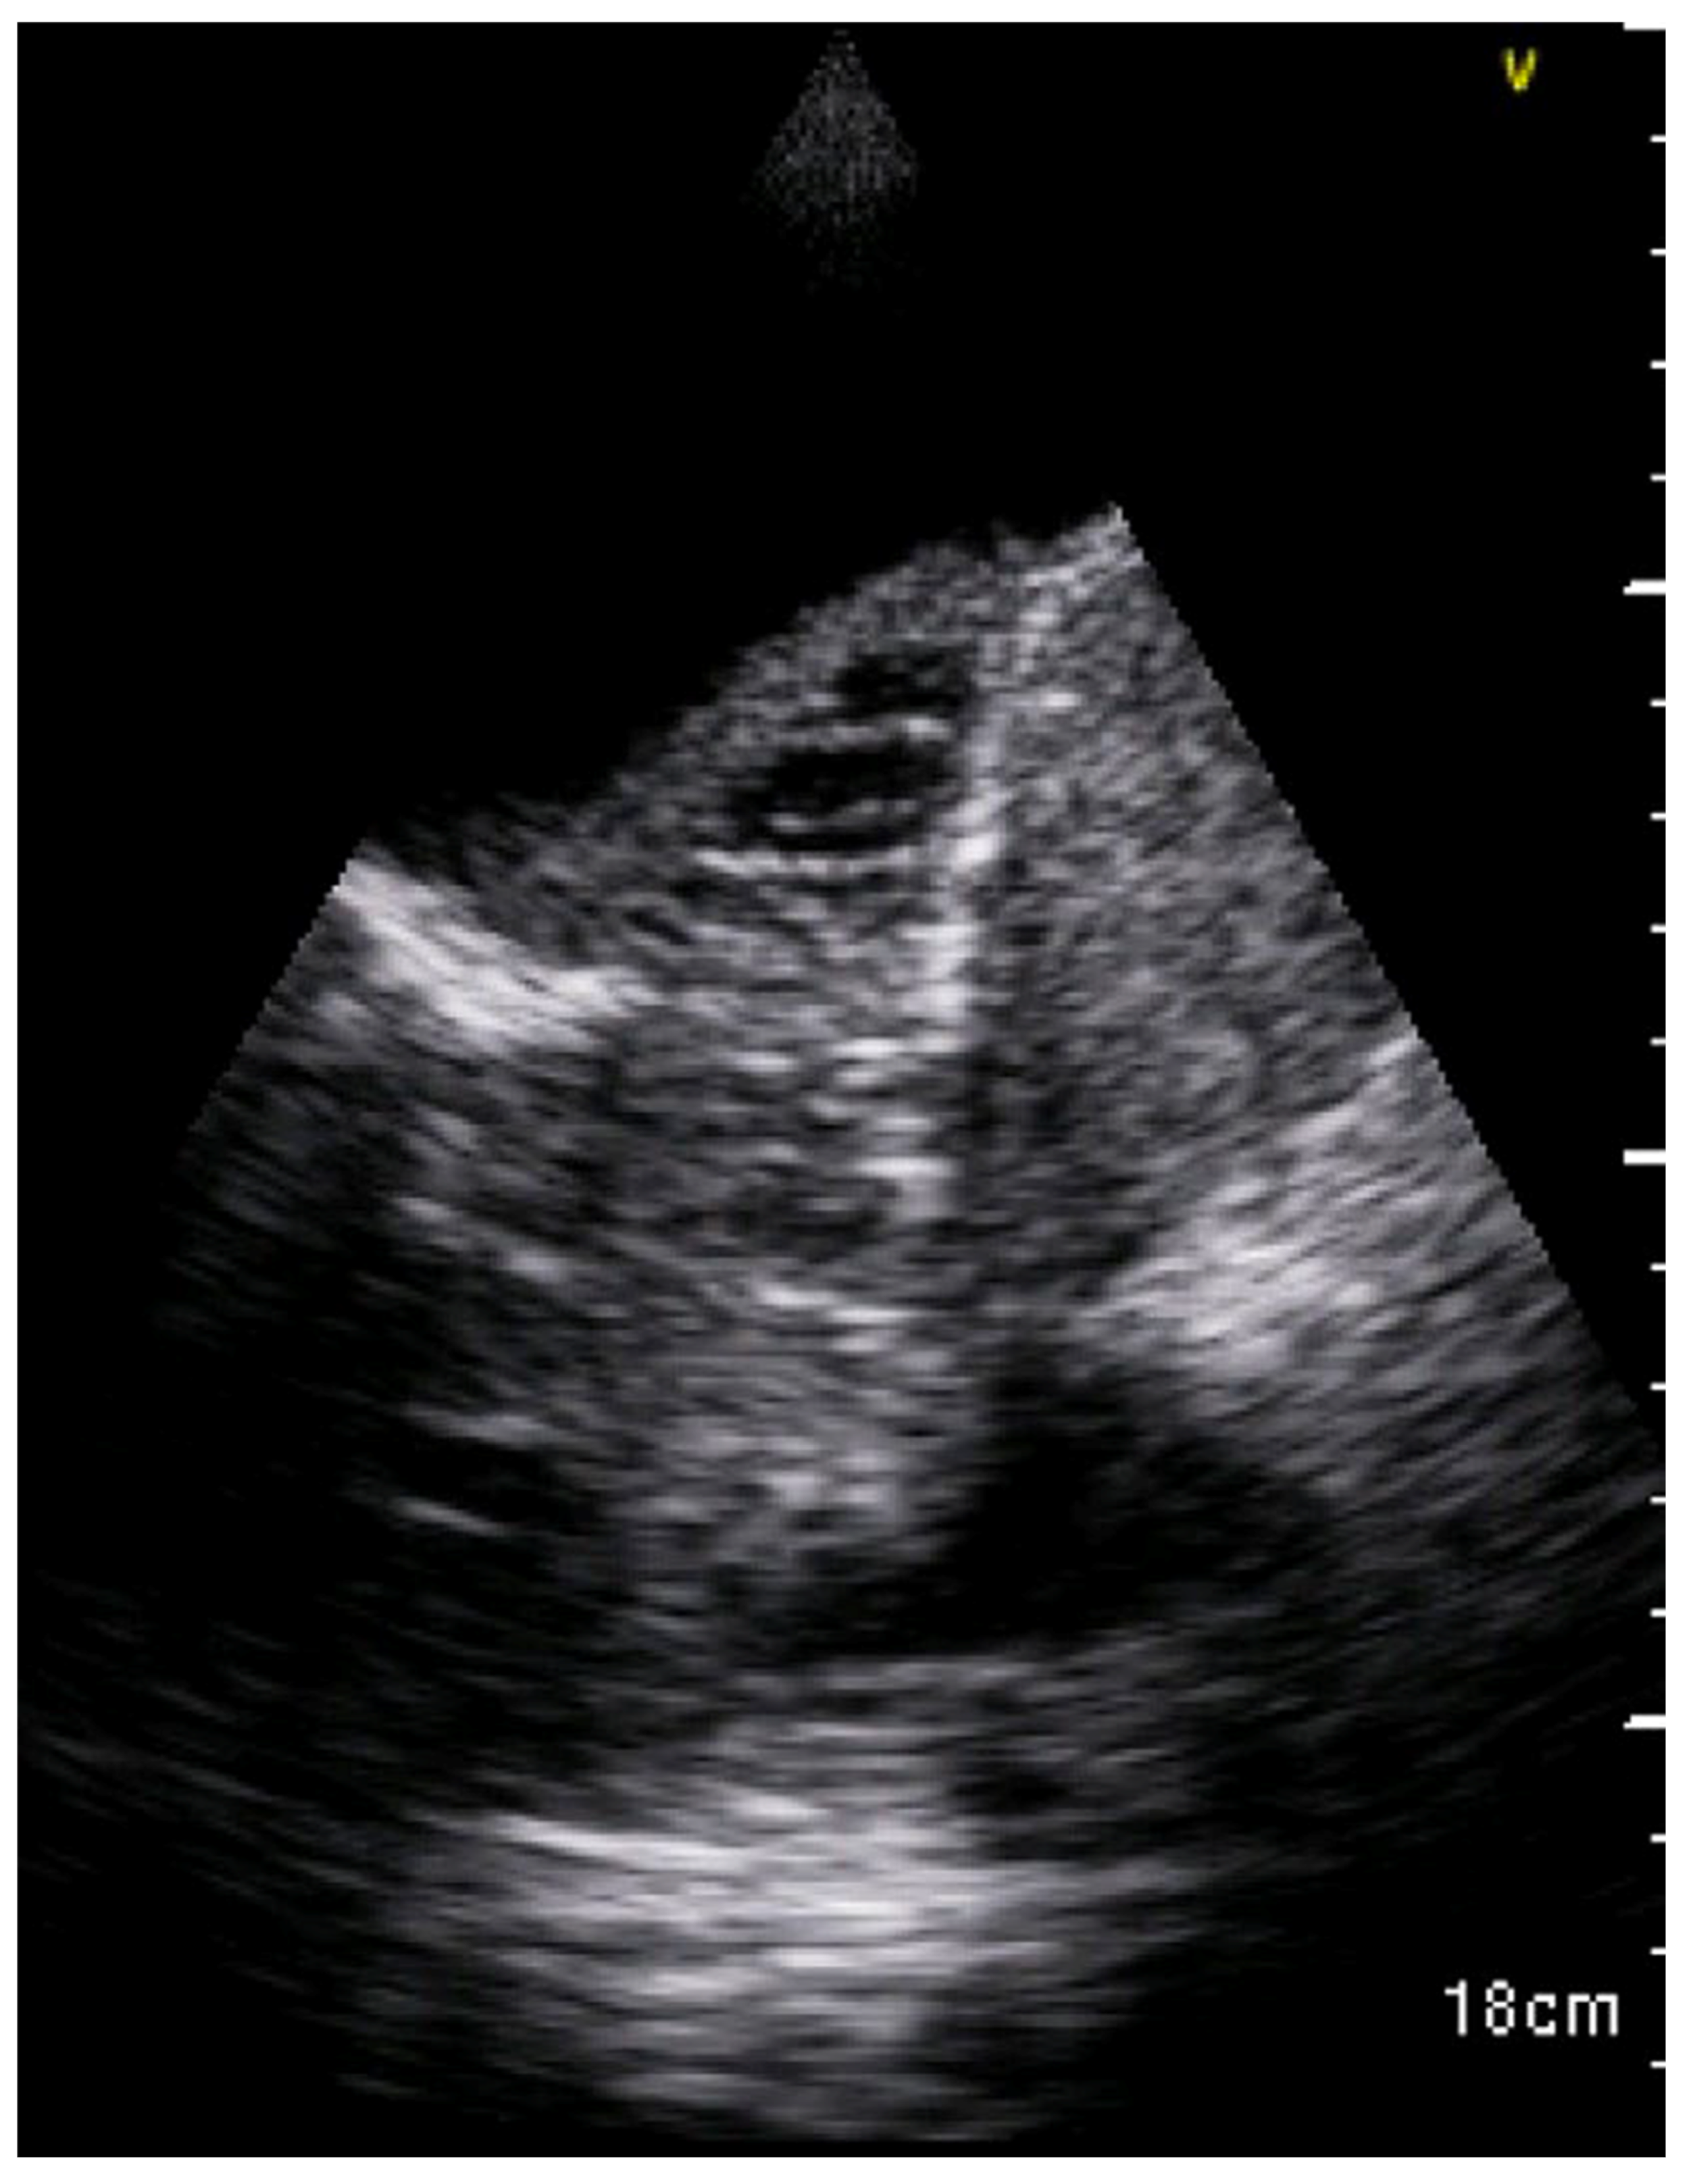

| Pleural effusion | Hypo- or anechogenic structure, delineated by the chest wall and the diaphragm [11,26] |